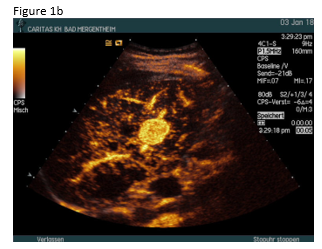

A 49 year old patient was admitted to the hospital for sepsis and shock of unknown origin. The patient presented with signs of sepsis and hemodynamic instability that justified an urgent approach including complex intensive care and intubation. Bedside ultrasound (US) found ascites and an abscess in the right liver lobe (9 cm) (Figure 1a). The patient was treated with broad-spectrum antibiotics and puncture and drainage of the abscess (Figures 1 a-c and 2 a-b). In addition, a biopsy was taken from the periphery of the lesion. A few days after the removal of the drainage the patient presented with a progressive elevation of liver enzymes. US revealed a cystic lesion measuring 30 mm that was proximal to the drained abscess (Figure 1a). Color Doppler Imaging (CDI) showed arterial flow inside the lesion, and contrast enhanced ultrasound (CEUS) showed early arterial enhancement and turbulent flow with a “to-and-fro” sign, suggestive of a pseudoaneurysm (Figure 1b). There was also a heterogeneously vascularized lesion with enhancing septae in the surrounding liver parenchyma (Figure 1c) . A few days later the patient presented with tachycardia and a drop of hemoglobin from 10 g/dl to 7 g/dl. US revealed spontaneous thrombosis of the pseudoaneurysm (Figure 1d) with intra - and perihepatic hemorrhage (Figure 1e).

Phlegmonous inflammation and abscess formations show variable and sometimes confusing US B-mode findings, which may change over time. The surrounding hypervascularitiy of abscesses may support the development of pseudoaneurysm after puncture and drainage in a few patients. On B-mode US pseudoaneurysms may appear like a cystic tumor, therefore CDI should be preferred as the primary screening technique for detection of vascular complications. The swirling colour pattern of the flow within the pseudoaneurysm that mimicks the "yin-yang" symbol (so called “to-and-fro” pattern) and the presence of high velocity are characteristic features of these lesions [(1-3)].